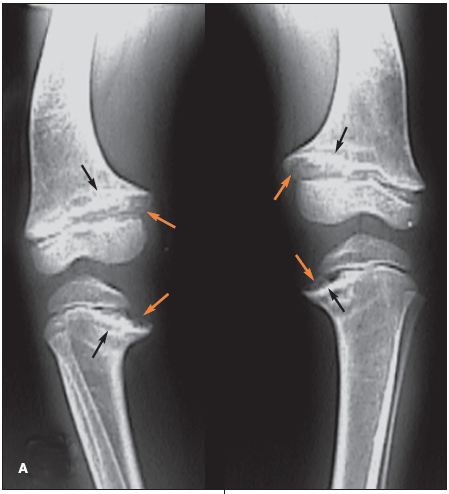

Radiographs of the patient's knees, the left knee alone, and the left wrist are obtained.

The radiograph of the knees shows bilateral genu varum and widening of all the tibial and femoral physes (A, orange arrows); there is also prominent sclerosis adjacent to the physes, primarily located in the medial portions of the metaphyseal tibiae and femora (A, black arrows). The radiograph of the left knee better demonstrates the physeal widening (B,orange arrows) and the juxtaphyseal sclerosis (B, black arrows). The radiograph of the left wrist shows widening of the distal radial physis with flaring of the distal radial and ulnar metaphyses (C,orange arrowheads); sclerosis adjacent to the radial and ulnar physes is most prominent in the distal radial metaphysis (C, black arrows). A prominent anterior costochondral junction caused by the preponderance of the maturing cartilage can also occur in persons with rickets.